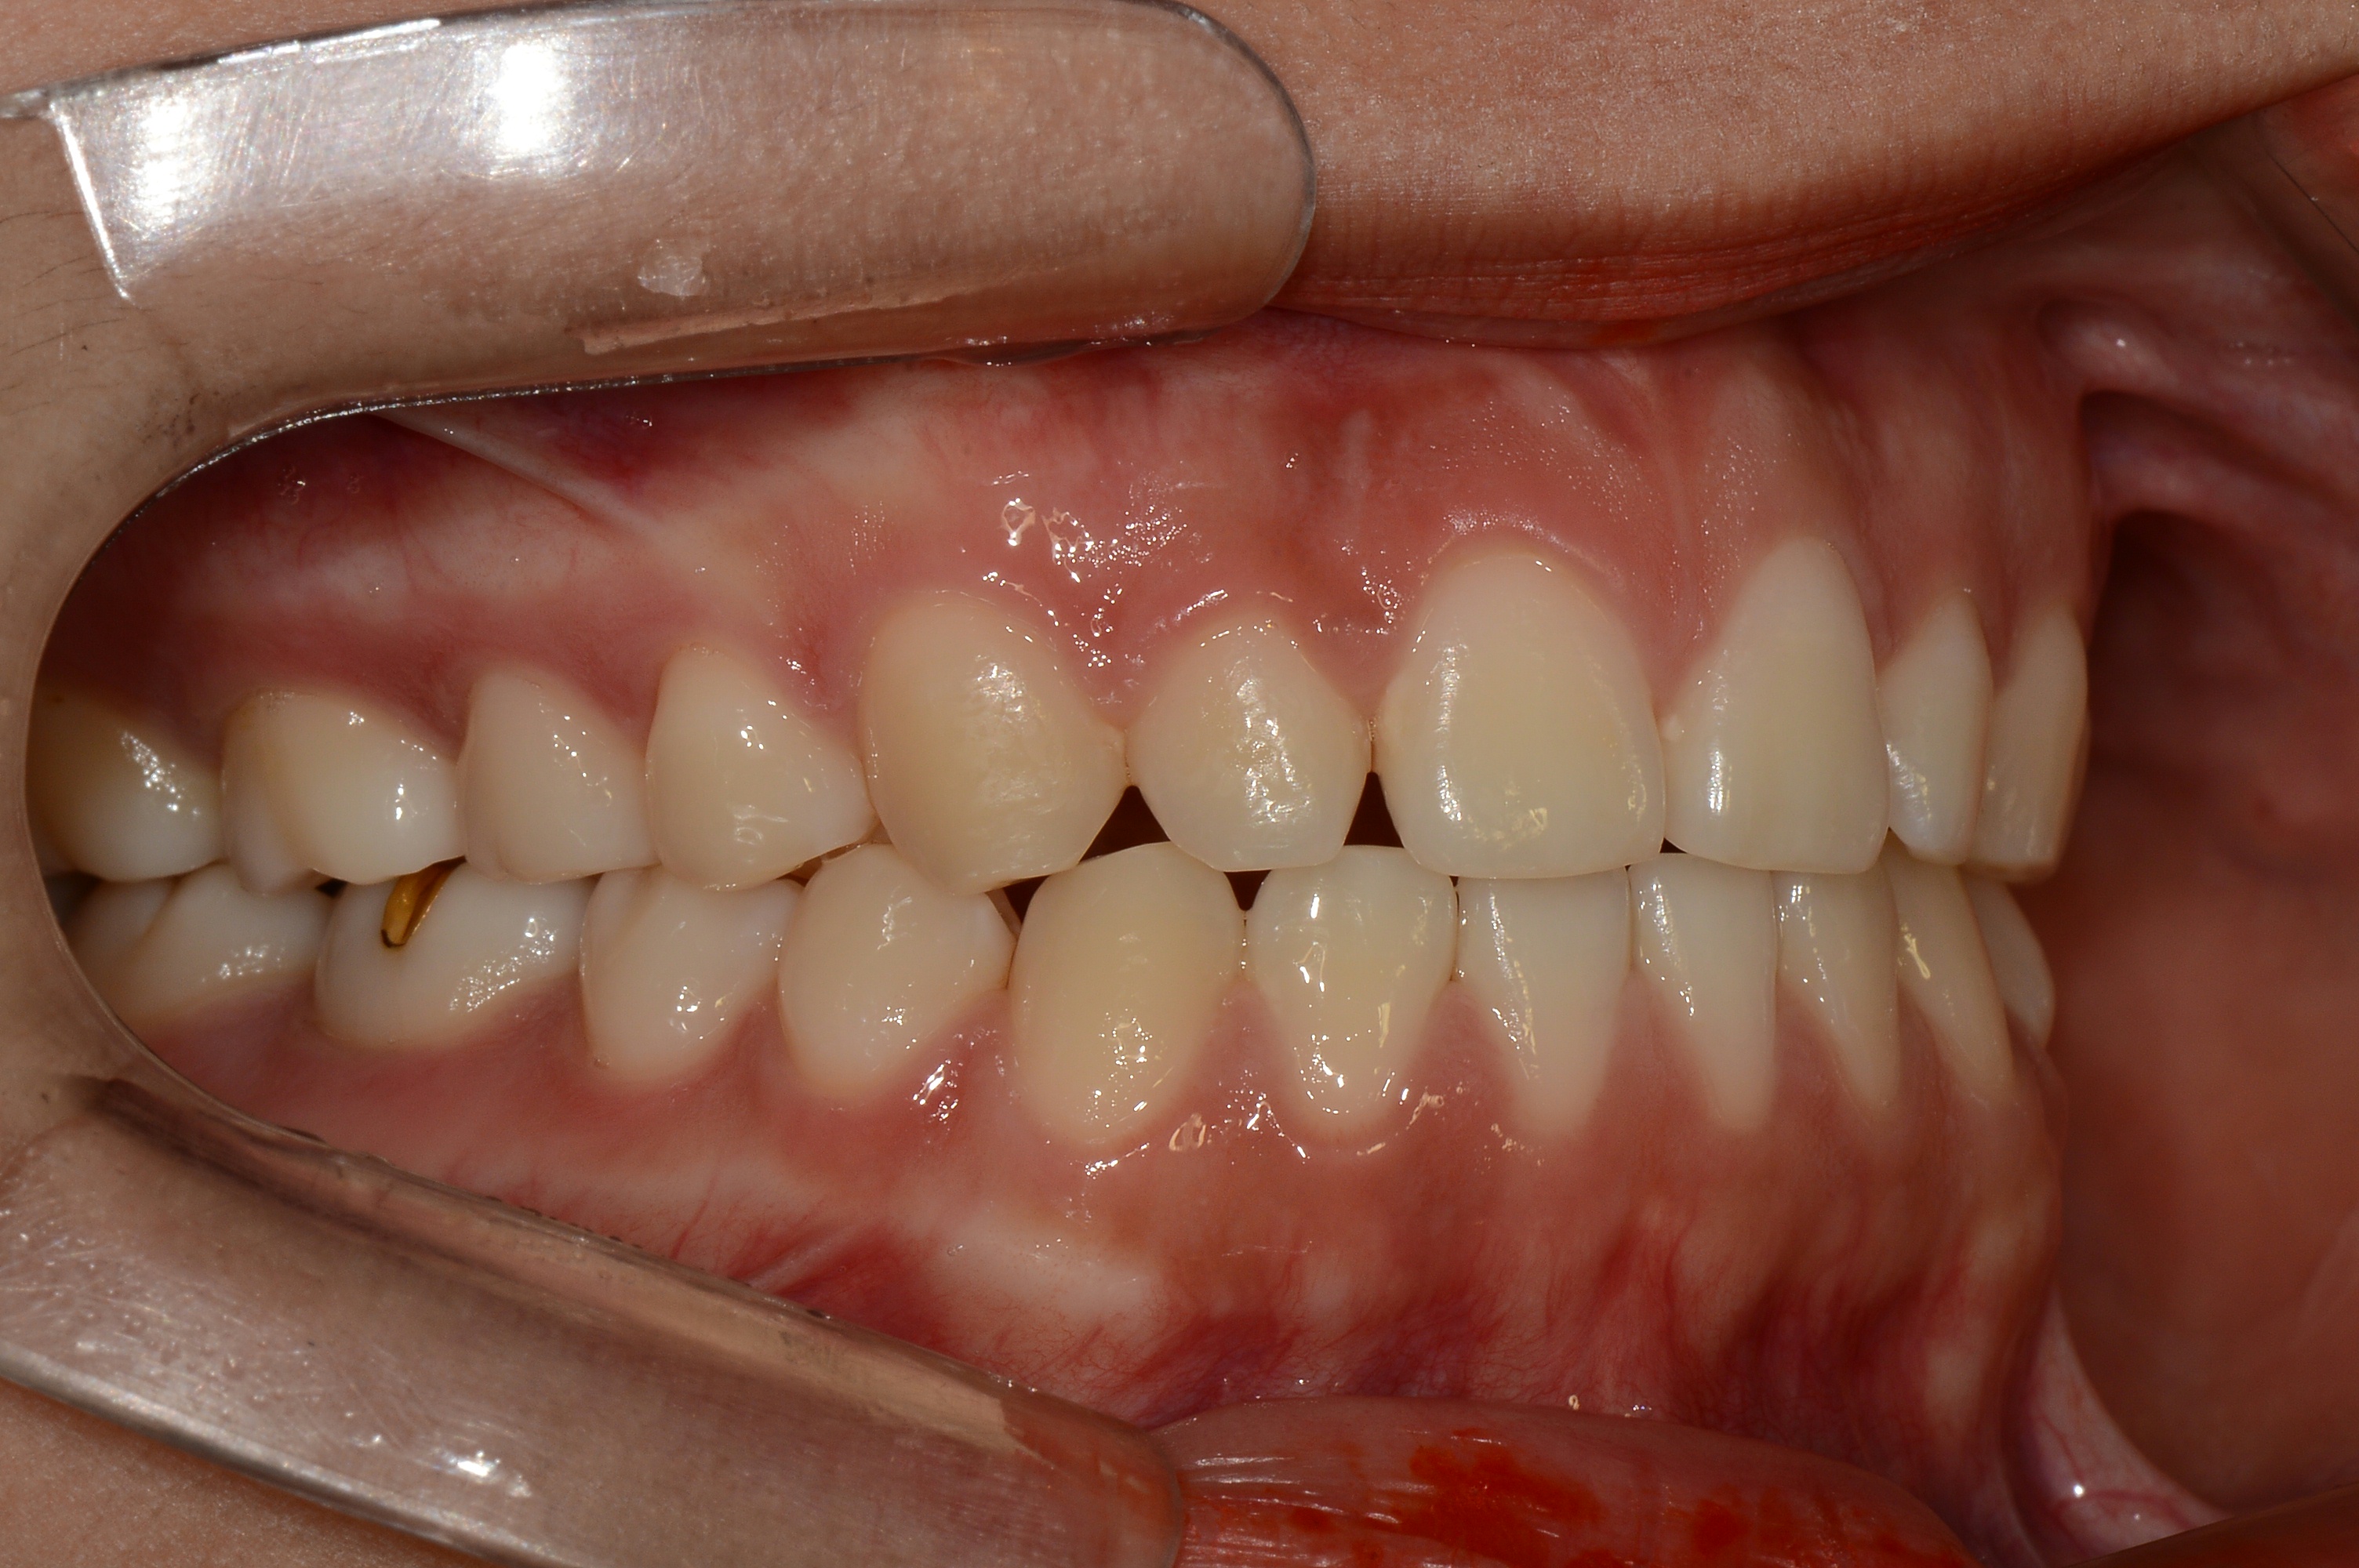

치료 후 사진입니다.